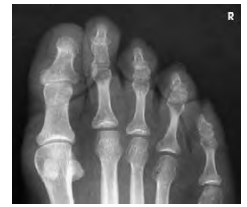

Structures shown

이 촬영법으로 얻는 영상은 발가락 14개의 골격과 발등뼈(metatarsals)의 원위부를 포함합니다. AP Axial 투사에서는 IP 관절과 MTP 관절 공간을 열어 보여줍니다.

- 발가락이 서로 분리되어야 합니다.

- 지골(phalanx) 회전이 없어야 하며, 연부조직의 폭과 중앙의 오목한 부분이 양쪽에서 대칭적으로 나타나야 합니다.

- IP 및 MTP 관절 공간이 AP Axial 투사에서 잘 열려 보여야 합니다.

- 연부조직과 뼈의 세부 구조가 뚜렷해야 합니다.